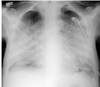

What is this chest radiograph showing? Which lung is affected? Which lobe is affected?

- Atelectasis

- It means that an entire lobe of the lung has lost its air, causing all alveoli it that lobe to collapse

- The left lung

- Inferior lobe of the left lung

These symptoms are indicative of what?

- Sail sign

- Less alveolar

- Surface means Hypoxia

- Decreased Lung Volume

- CO2 remains normal

Atelectasis

Which structure is moving as a result of atelactasis?

The left diaphragm